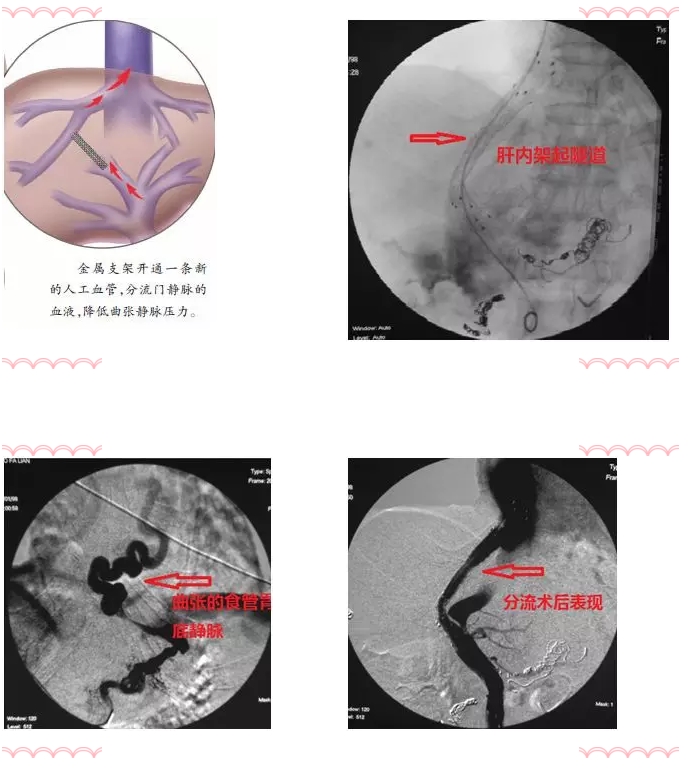

朱亮副主任医师表示:其实解决门静脉压力高的问题,就像大禹治水一样,光堵是不行的,堵永远不如疏!“隧道工程”是TIPS手术的关键技术点:在肝静脉、门静脉之间建立“隧道”,部分门静脉血流直接进入肝静脉,降低了门静脉压力,门体压力梯度降低了,出血自然停止了。

TIPS手术可称之为最难的介入手术,因其手术难度大、风险高,成功率低,多被介入医师放弃,但在治疗门静脉高压所致上消化道出血中独树一帜,效果显著。

门脉高压是肝硬化的主要并发症之一,经颈静脉肝内门体分流术(TIPS)已广泛用于治疗门脉高压并发症,如食管静脉曲张出血、顽固性腹水、肝性胸水、2型肝肾综合征、布加综合征和肝窦阻塞综合征。